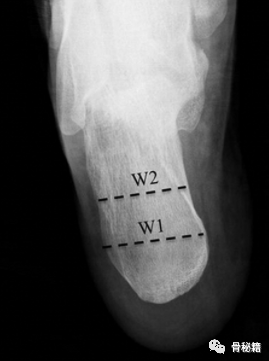

2. 轴位片。主要用于评价跟骨外翻畸形程度、宽度、后关节面的塌陷及与跗骨窦的相对位置。